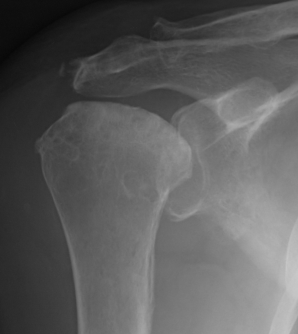

Classification / Cruess modification of Ficat-Arlet

Stage I - pre-xray change / diagnosed on MRI

Stage II - sphericity maintained / sclerotic changes in superior central head / crescent sign

Stage III - mild flattening articular surface

Stage IV - significant humeral collapse with loss integrity joint surface

Stage V - degeneration extends to involve glenoid